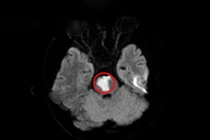

Nhồi máu não tuổi 17 tuy hiếm gặp nhưng đây là trường hợp cảnh báo người dân về tầm quan trọng của việc theo dõi và chăm sóc sức khỏe bản thân, đặc biệt là không nên tự ý điều trị tại nhà khiến bệnh lý trầm trọng hơn.